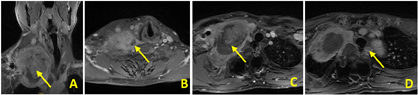

术后患者右上肢无感觉障碍,运动查体同术前,桡动脉搏动有力。颜面部可见右上睑下垂、面部少汗、眼窝凹陷等轻度霍纳综合征(Horner’s sign)表现,考虑为术中扰动颈交感干导致其功能减退所致。磁共振平扫+增强复查可见原颈部肿物消失,右锁骨下动脉通畅未见狭窄,臂丛神经完整可见。术后恢复良好,痊愈出院。出院后继续予以规律局部放疗一疗程(共35次),未予全身化疗。术后6个月随访右手内在肌肌力V级,无活动障碍,颜面部症状明显缓解。影像学检查未见原部位肿瘤复发(图6)。